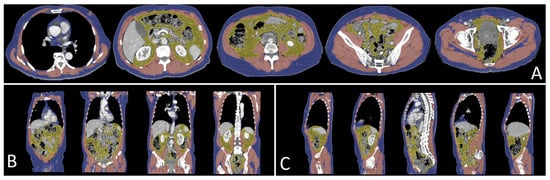

- Decazes, P.; Tonnelet, D.; Vera, P.; Gardin, I. Anthropometer3D: Automatic Multi-Slice Segmentation Software for the Measurement of Anthropometric Parameters from CT of PET/CT. J. Digit Imaging 2019, 32, 241–250. [Google Scholar] [CrossRef]

- Lee, Y.S.; Hong, N.; Witanto, J.N.; Choi, Y.R.; Park, J.; Decazes, P.; Eude, F.; Kim, C.O.; Chang Kim, H.; Goo, J.M.; et al. Deep Neural Network for Automatic Volumetric Segmentation of Whole-Body CT Images for Body Composition Assessment. Clin. Nutr. 2021, 40, 5038–5046. [Google Scholar] [CrossRef] [PubMed]